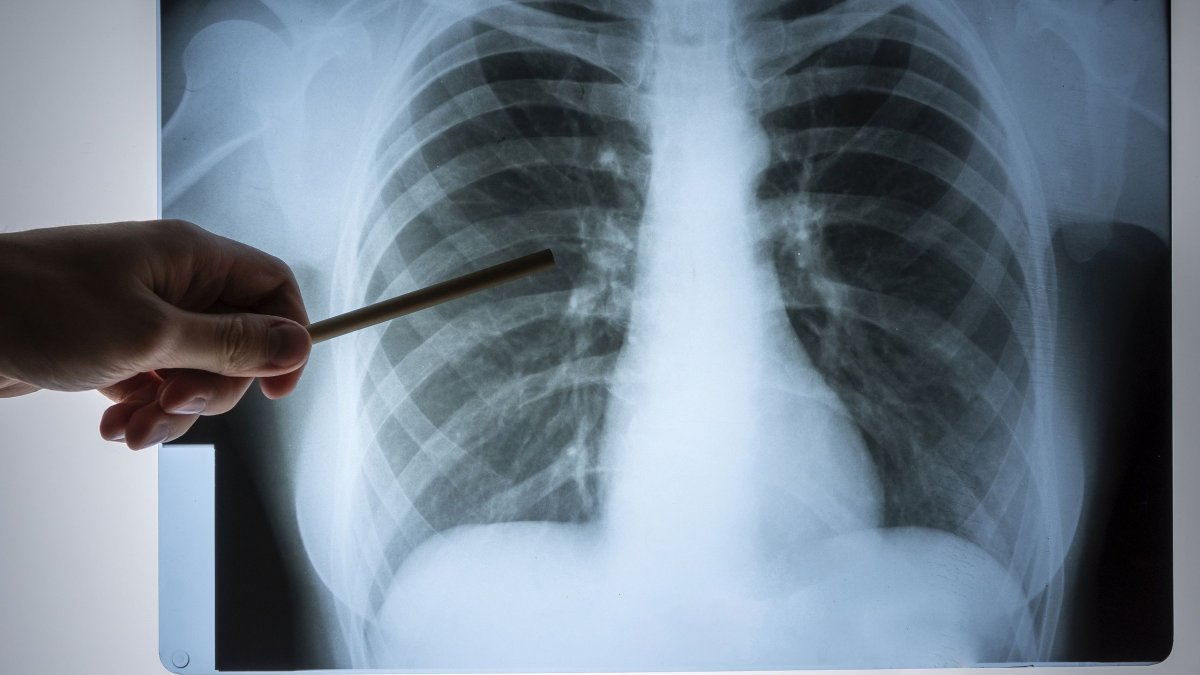

Η παραγωγή ιδρώτα με υψηλή περιεκτικότητα σε ηλεκτρολύτες είναι συνήθως το πρώτο σύμπτωμα που παρατηρείται από τον ασθενή με κυστική ίνωση, αφού τα συμπτώματά της επηρεάζουν πολύ διαφορετικά κάθε άνθρωπο.

Η παραγωγή ιδρώτα με υψηλή περιεκτικότητα σε ηλεκτρολύτες είναι συνήθως το πρώτο σύμπτωμα που παρατηρείται από τον ασθενή με κυστική ίνωση, αφού τα συμπτώματά της επηρεάζουν πολύ διαφορετικά κάθε άνθρωπο.